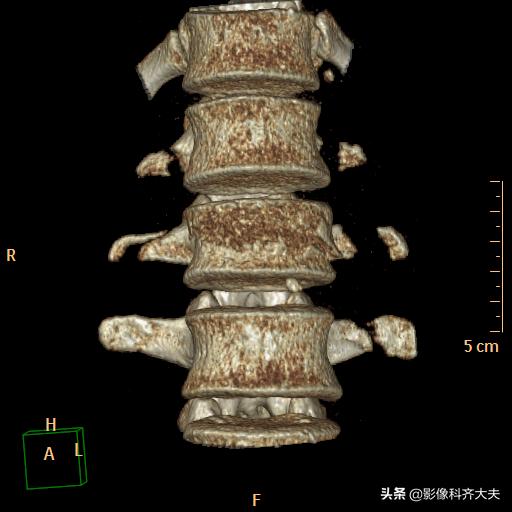

腰二横突骨折

VR重建